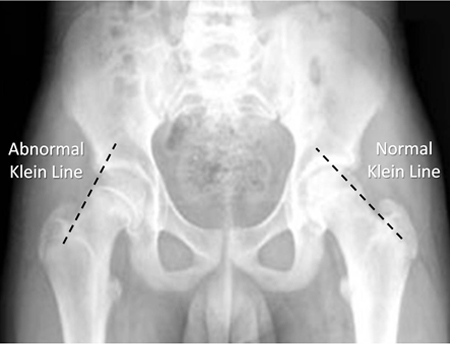

Tanı ve Radyoloji; Tanıda altın standart ön-arka (AP) ve kurbağa pozisyonu (frog-leg) yan kalça grafileridir.

- Klein Hattı: AP grafide femur boynunun üst kenarından çizilen hattın, femur başı epifizinin bir kısmını kesmesi gerekir. Eğer kesmiyorsa “kayma” var demektir (Trethowan belirtisi).